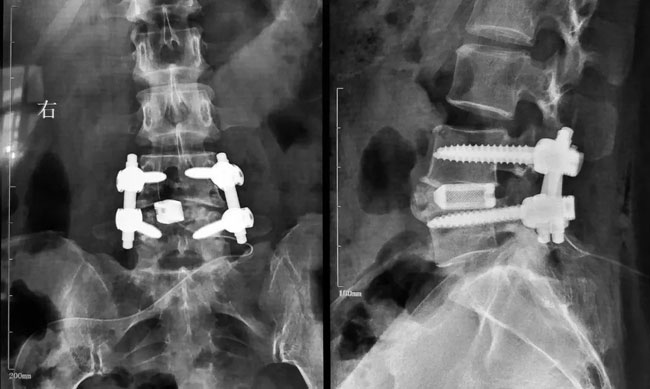

高放射线可见性可实现更好的轮廓显示,便于术中、术后清晰地观察融合器,评估椎体终板与植入物的接触情况,以及骨融合情况。

X射线清晰可见植入物,CT扫描无散射,MRI伪影减少,无钽标记物散射。